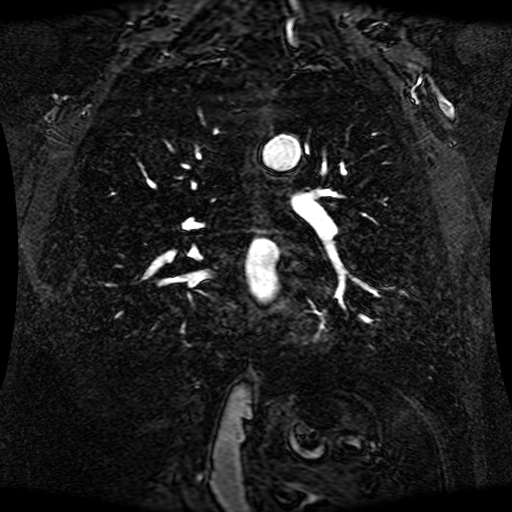

These magnetic resonance angiography (MRA) images show coronal slices acquired from consecutive anteroposterior positions within the torso. The study was performed on a 1.5T General Electric (GE) Signa imaging system with gadolinium-contrast-enhancement for visualization of the cardiopulmonary vasculature. The pulse sequence used was a 3D time-of-flight fast spoiled gradient recalled acquisition in steady state (FSPGR, TR=6.3, TE=1.4, NEX=1, FOV = 40cm, slice thickness = 1.2mm).

This sample image contains 76 frames. It is available in DICOM format (E1154S7I.dcm), as an animated GIF (E1154S7I.gif), as .ogg, .mp4, .webm, and .swf animations (one of which is shown above), or as individual PNG-format frames (see below).